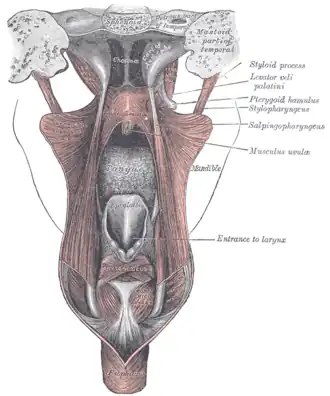

Dissection of the muscles of the palate from behind. (Choanae visible at center top.) | |

The choanae are separated in two by the vomer.